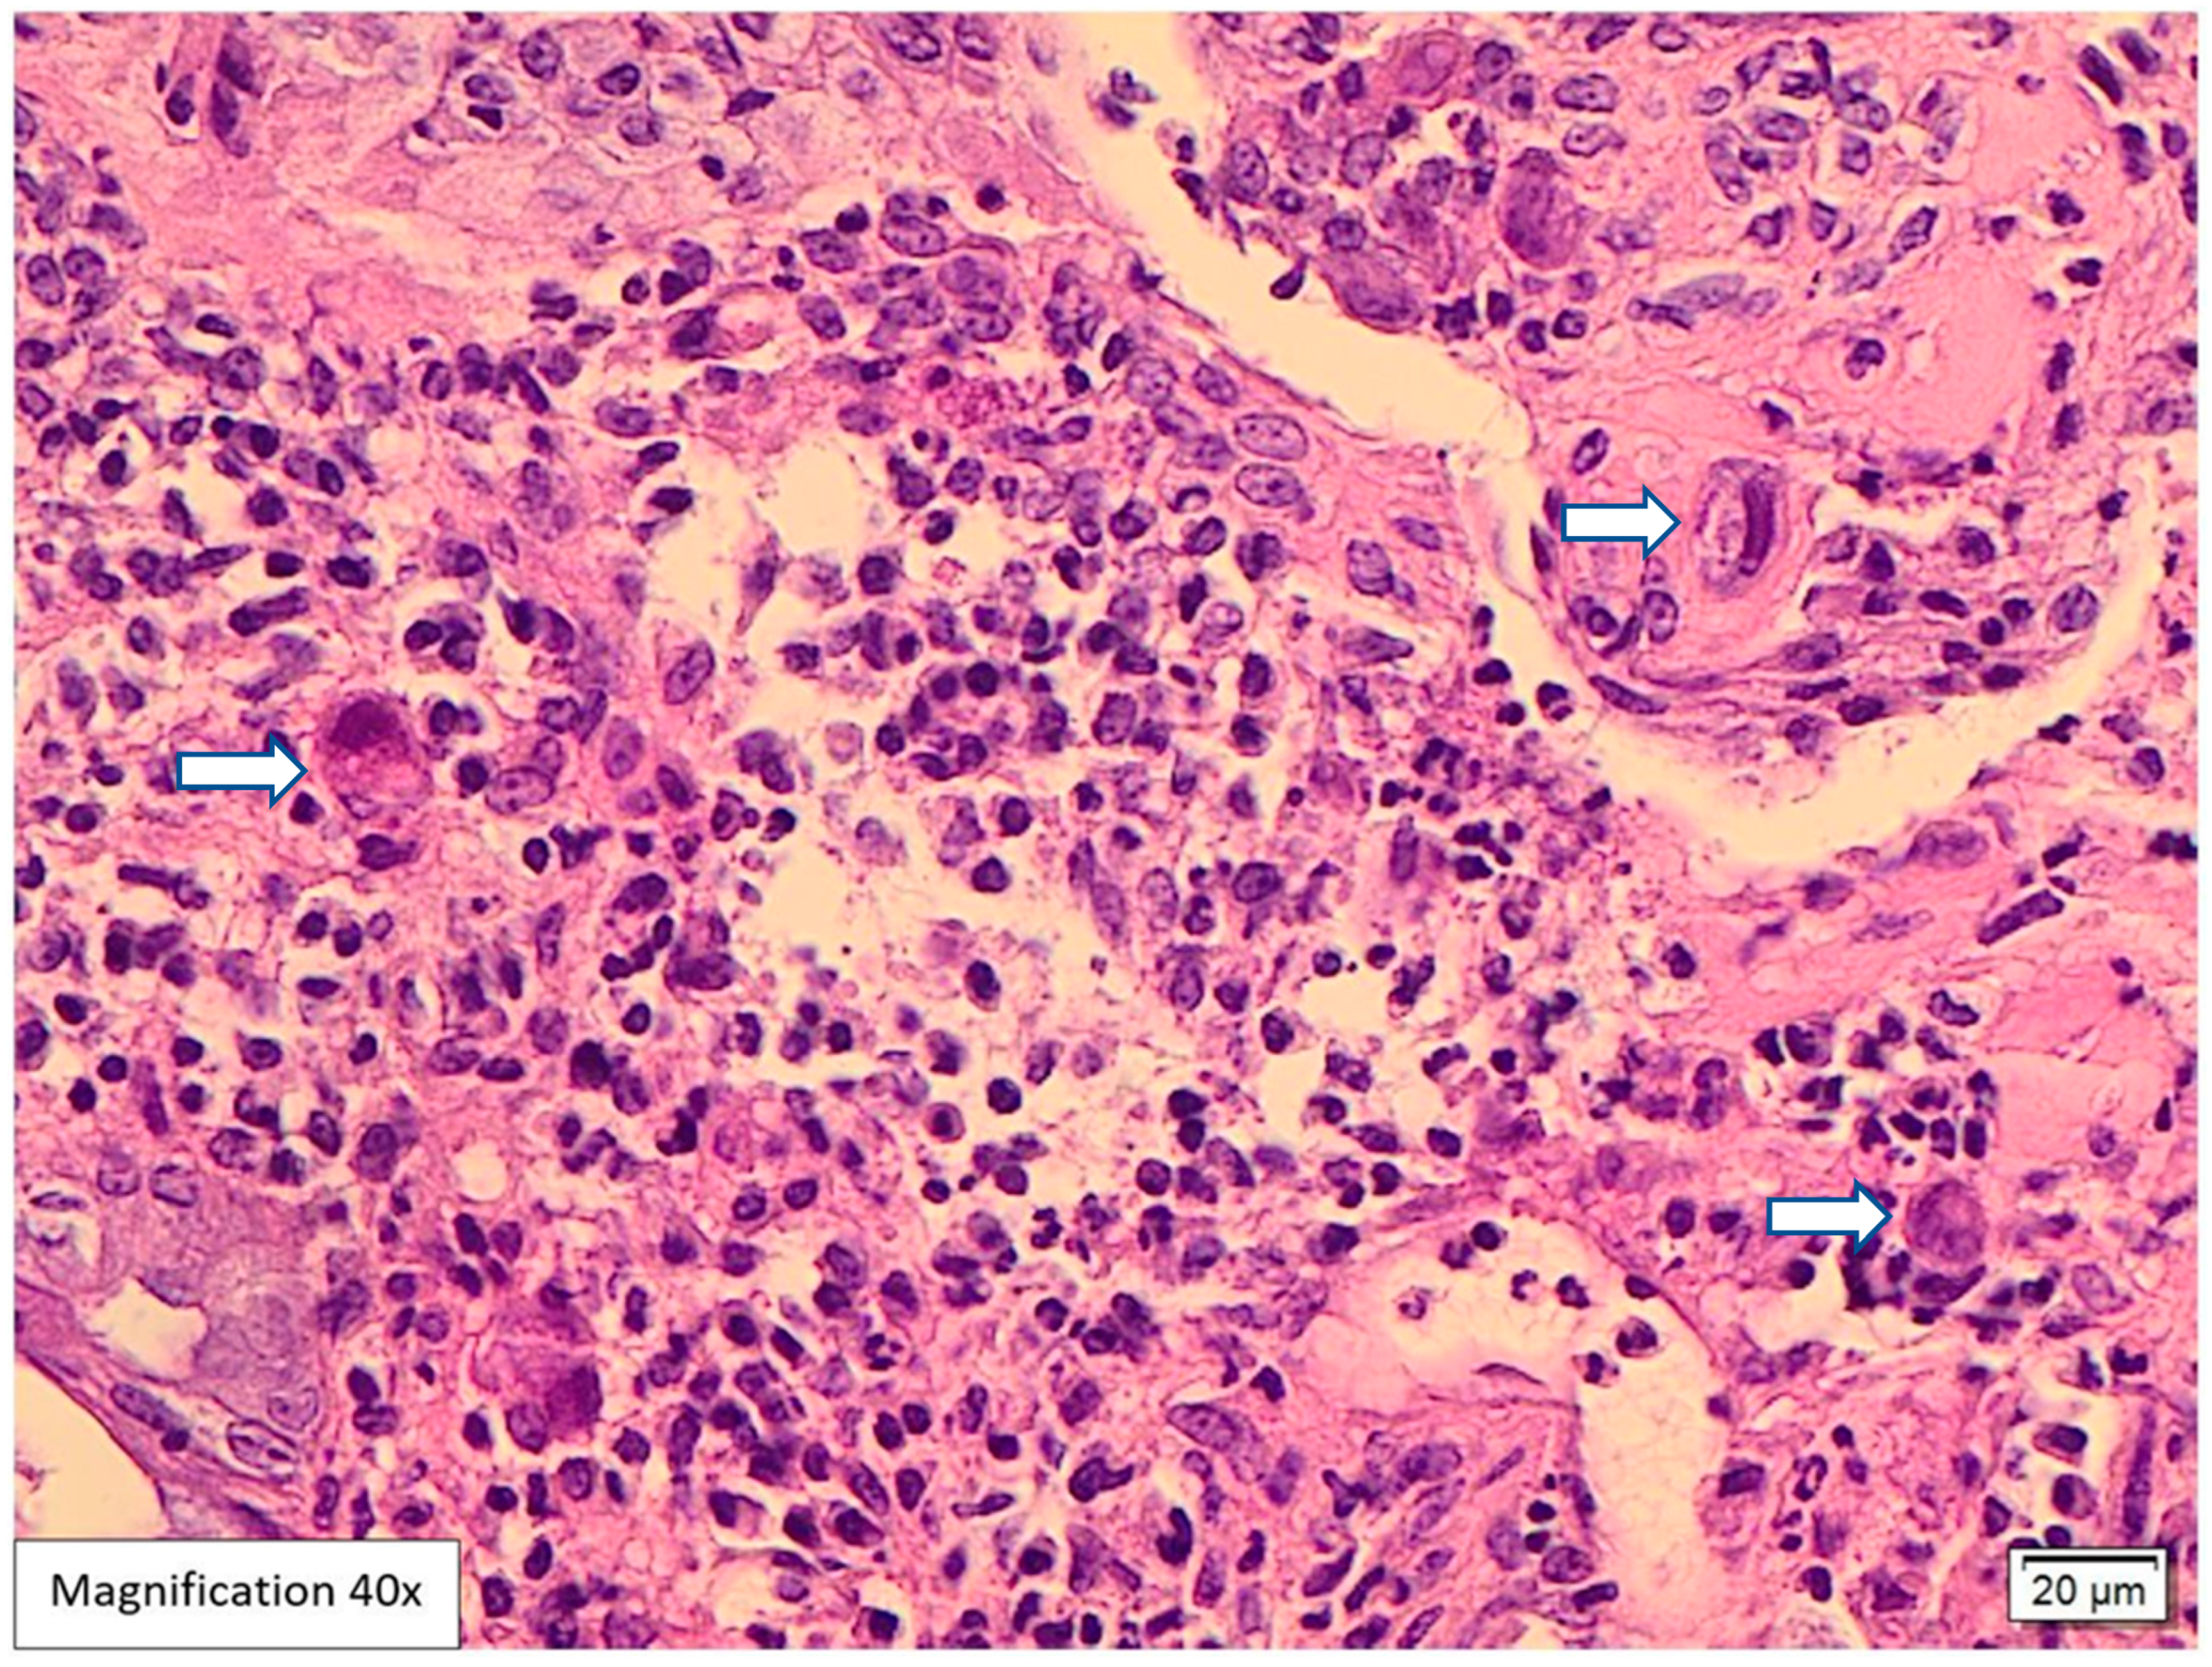

Case Presentation